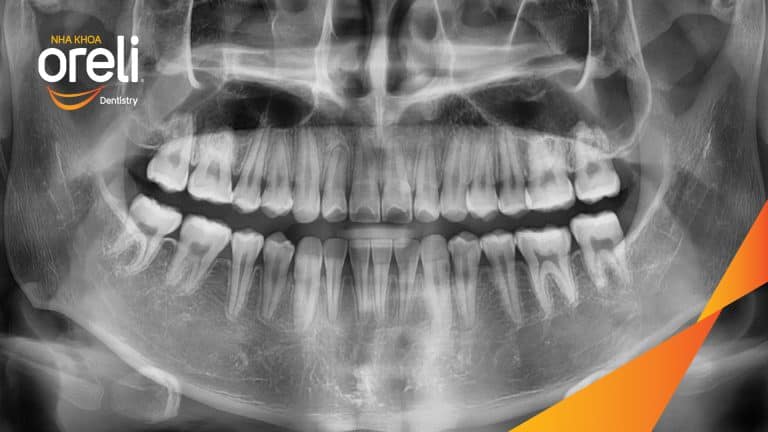

Ca niềng chỉnh chen chúc hẹp hàm nặng cả trên và dưới – Kết quả điều trị thực tế tại nha khoa Oreli Niềng răngChen chúc Xem thêm